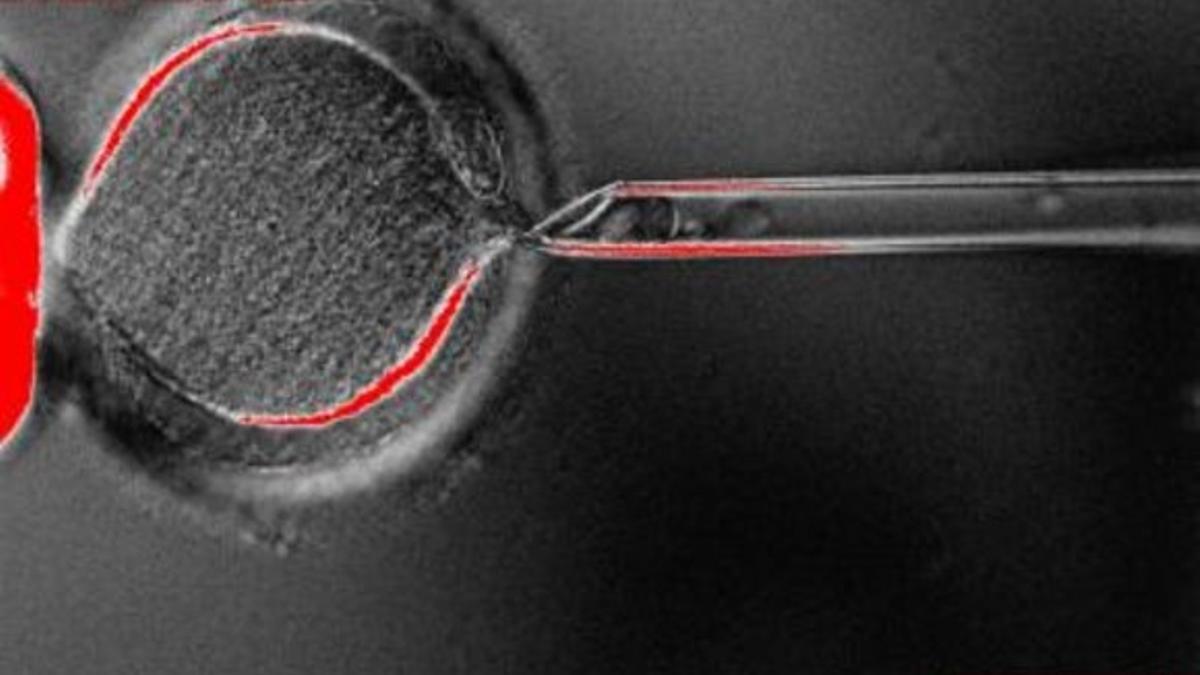

Captación de material genético en un óvulo. / periodico

Los investigadores de Oregón han realizado exactamente una transferencia nuclear de células somáticas (SCNT, según sus siglas en inglés), una técnica mediante la cual el núcleo de una célula adulta de un donante se transfiere al interior de un óvulo al que previamente se le ha extirpado el núcleo. El proceso provoca que la célula resultante, con un ADN idéntico al de la célula del donente, empiece a dividirse como si fuera un embrión.